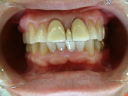

初診の状態とセット時の状態